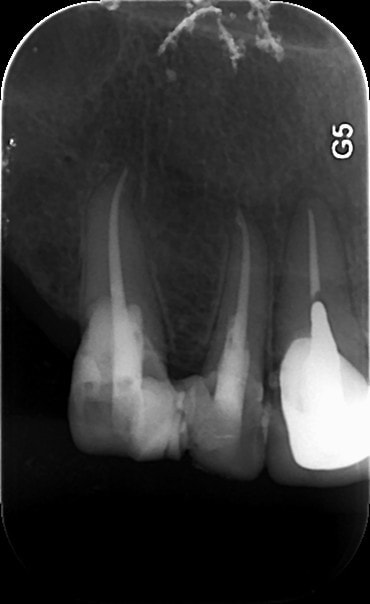

1   02022015 xhyug0 - Eugenol

3   02022015 athoja - Eugenol

2   02022015 jomvv1 - Eugenol

4   06022015 zewfwa - Eugenol

5   06022015 uym87j - Eugenol